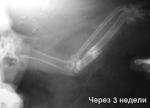

Голубь, висит крыло, подозрение на перелом.

post-46676-1382624966_thumb.jpg

Снимок до репозиции отломков

post-46676-1382624988_thumb.jpg

Снимок через 3 недели фиксации

Хороший пример отдельного снимка крыла. На левом фото - снимок до репозиции отломков. Хорошо виден закрытый косой смещенный в двух плоскостях перелом локтевой кости, ближе к проксимальному концу. На правом фото - он же, после репозиции, фиксации в течение трех недель. Совмещение отломков не очень удачное, из-за этого несколько замедлена консолидация перелома. Репозицию и фиксацию делала подобравшая птицу человеческий врач-хирург. Неидеальные результаты объясняются в первую очередь тем, что она сначала пыталась найти опытного ветеринара, за это время (четверо суток) концы отломков уже немного покрылись тканью костной мозоли, а сами отломки успели даже несколько схватиться. Но в целом итог хорош - птица вполне нормально полетела спустя еще три недели.